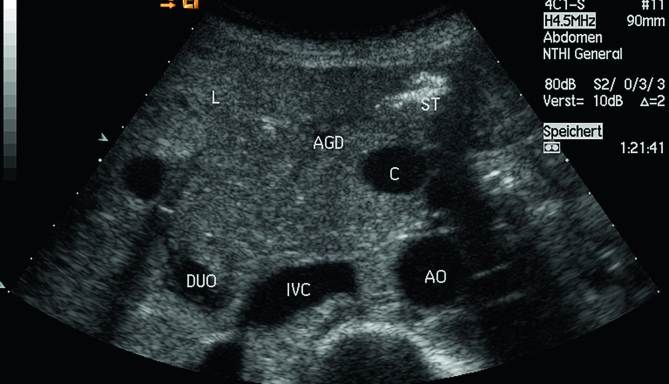

Reliable and reproducible measurement methods have been established, and reference values are used in almost all scientific disciplines. Knowledge of reference values is crucial to distinguish physiological from pathological processes and, therefore, subsequently, for the clinical management of patients. Image storage and documentation of measurements and normal findings should be part of quality assurance in imaging. This paper aims to review the published literature and provide current knowledge of sonographic measurements and reference values of the pancreas. Moreover, the role of clinical influencing factors such as age, gender, constitution, and ethnicity is also analyzed.